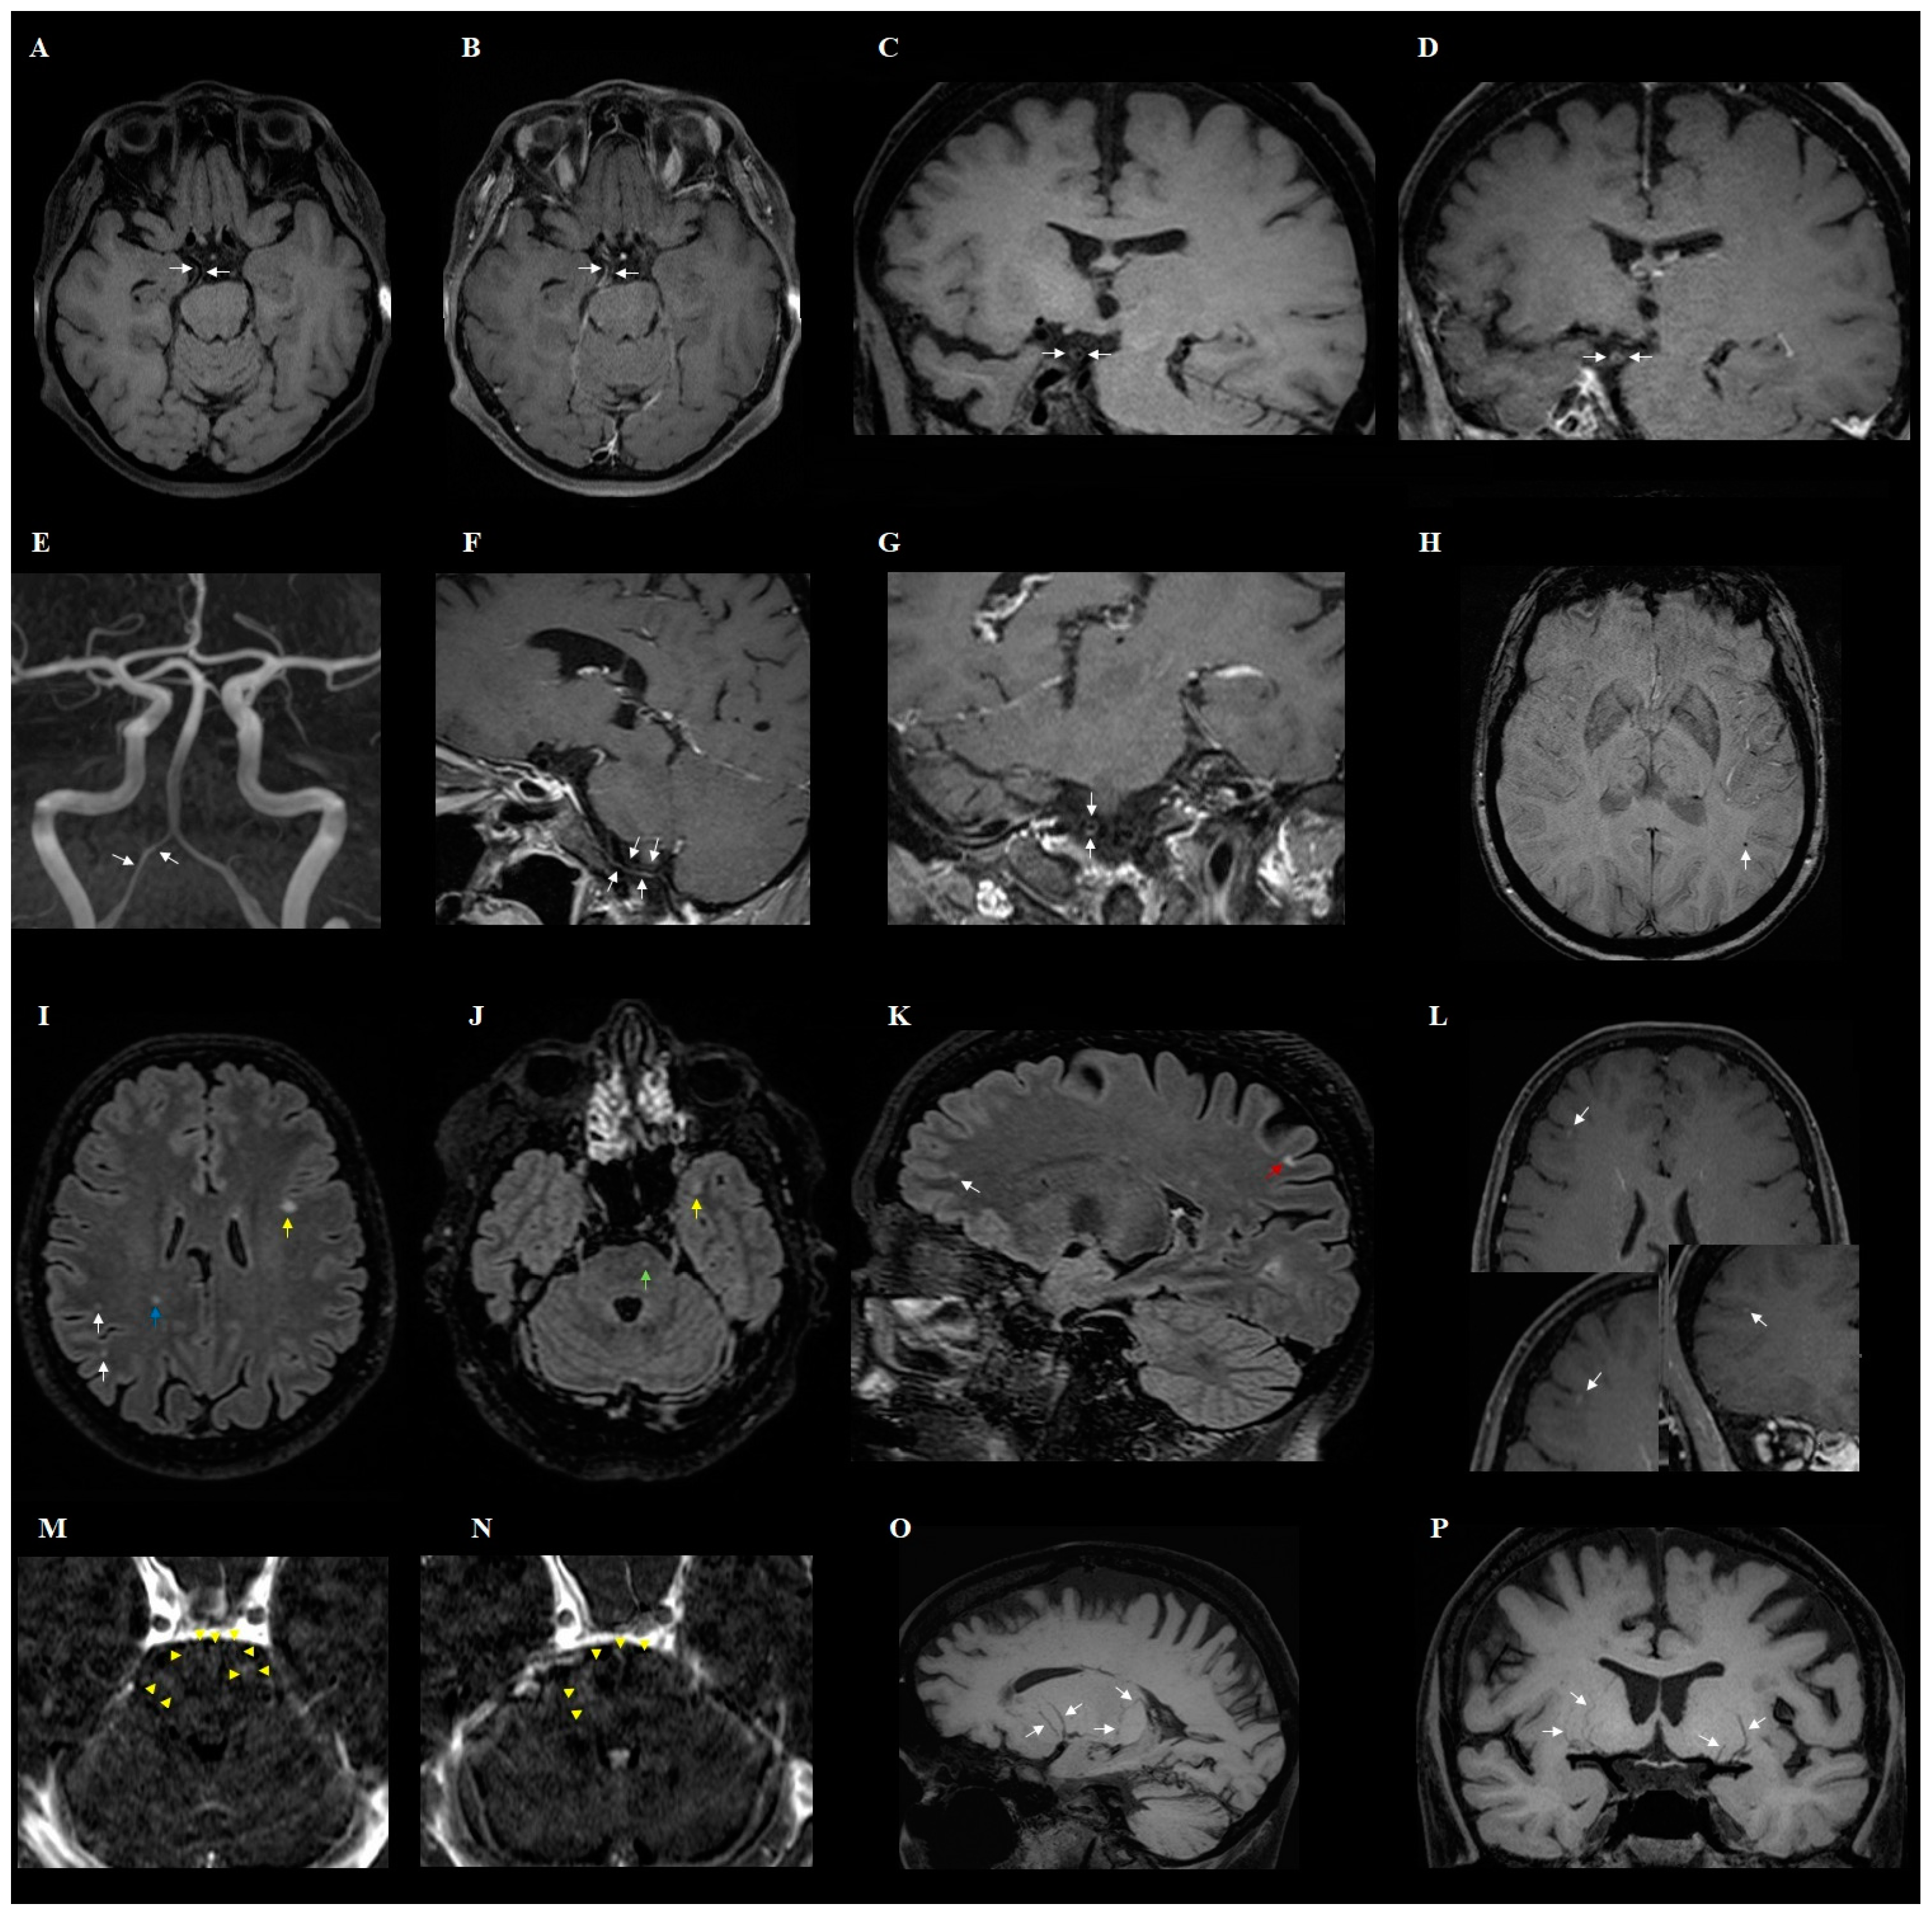

| Presence of engorgement of deep medullary veins or perivascular enhancement (Figure 2) | 3 | 13% | ||

| Enhancement of the pia mater in T1-weighted images (space black blood) | 3 | 13% | ||

| Presence of inflammatory (concentric) vessel thickening in VWI images | 7 | 30% | ||